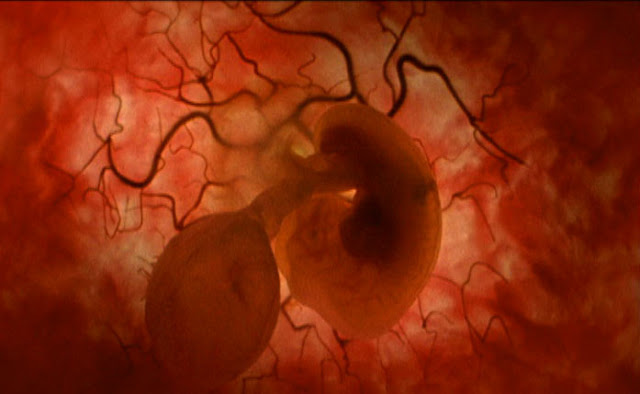

Paso a paso. El feto flota suavemente en el interior del vientre materno.

Tercer mes y primer susto. Se trata de una recreación por ordenador realizada a partir de ecografías reales en 3D y 4D.

Paso a paso. El feto flota suavemente en el interior del vientre materno.

Tercer mes y primer susto. Se trata de una recreación por ordenador realizada a partir de ecografías reales en 3D y 4D.